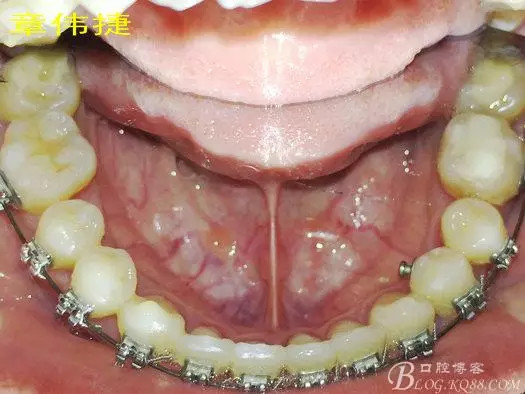

矯治八個(gè)月術(shù)中資料:

經(jīng)過8個(gè)月的治療,患者的間隙已完全關(guān)閉,患者非常滿意,后期進(jìn)入精細(xì)調(diào)整階段,建議做舌體修整術(shù),防止復(fù)發(fā)。